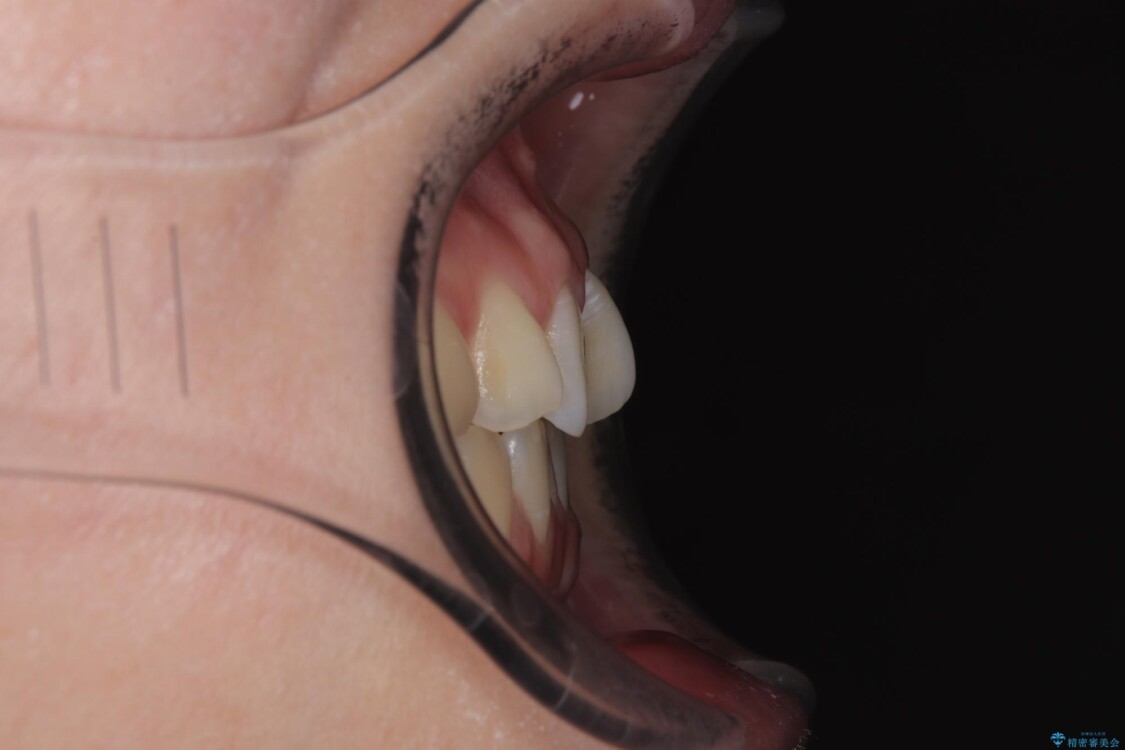

診察の結果、上下の前歯部に**叢生(そうせい/歯のガタガタ・重なり)**が認められました。

特に上の前歯にはねじれや重なりがあり、審美的にも清掃性にも影響している状態でした。

治療前

• 前歯のねじれ・ガタガタを10か月で改善!20代女性の矯正治療|クリアブラケットでむし歯になりにくい歯並びへ改善 治療前画像